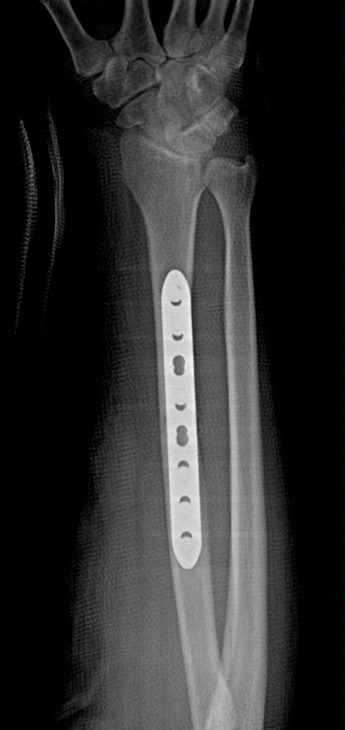

Radial Shaft Fracture Fixation with Plate